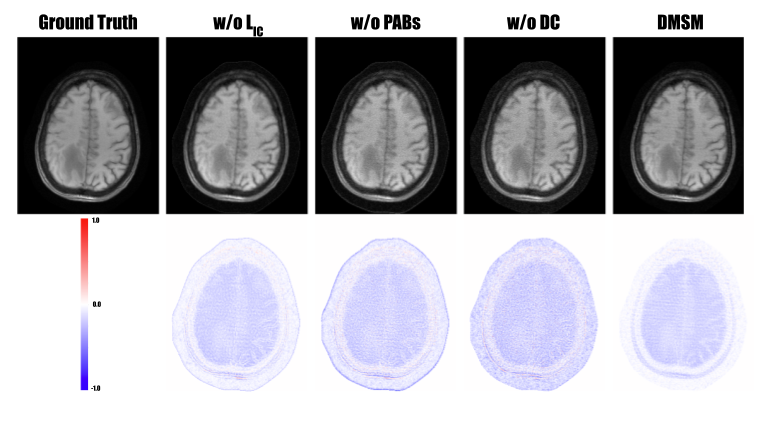

Impact of diffusion self-supervision across different domains: To assess the effectiveness of our multi-domain self-supervised learning strategy for the diffusion model, we compared DMSM’s performance using only single-domain self-supervision. Figure 6 provides a visual comparison between models trained with only k-space self-supervision (2nd column) and those incorporating both k-space and image-domain self-supervision (last column). The results demonstrate that multi-domain self-supervision significantly improves reconstruction quality and reduces error. The quantitative comparison in Table IV further supports this observation, showing a performance drop from 38.15 dB to 36.39 dB when image-domain self-supervision is omitted. Notably, the model failed to converge when trained with image-domain self-supervision alone, underscoring the necessity of incorporating both domains for effective self-supervision. The results are not reported for image-domain self-supervision for this reason as well.

Refer to caption

Figure 6: Visualization of ablation studies on DMSM components. The DMSM reconstruction (top row) and the corresponding error map (bottom) row are shown. Results on excluding the image-domain loss (2nd column), LHAN (3rd column), and DC layer (4rd column) are visualized for a FLAIR example from fastMRI with 4×\times× acceleration setting.

Impact of Sub-Network Structure in DMSM: The backbone network in DMSM comprises two key modules: LHAN and DC. Here, we extensively evaluate the contribution of each component. Figure 6 presents a visual comparison between reconstructions without PAB in LHAN (3rd column) and with PAB in LHAN (last column). As shown, PAB effectively extracts features using parameter-free attention, significantly reducing reconstruction error. Table IV and Figure 7 provide a detailed quantitative analysis of different numbers of PABs in LHAN. Performance is suboptimal without PAB (i.e., number of PAB = 0) but improves and converges when the number of PAB reaches to about 4. Additionally, we examine the impact of DC in the diffusion process. Both the visual examples in Figure 6 and the quantitative results in Table IV show that removing DC severely degrades performance, decreasing from 39.15 dB to 28.82 dB. This highlights the critical role of data consistency in ensuring effective diffusion-based reconstruction.